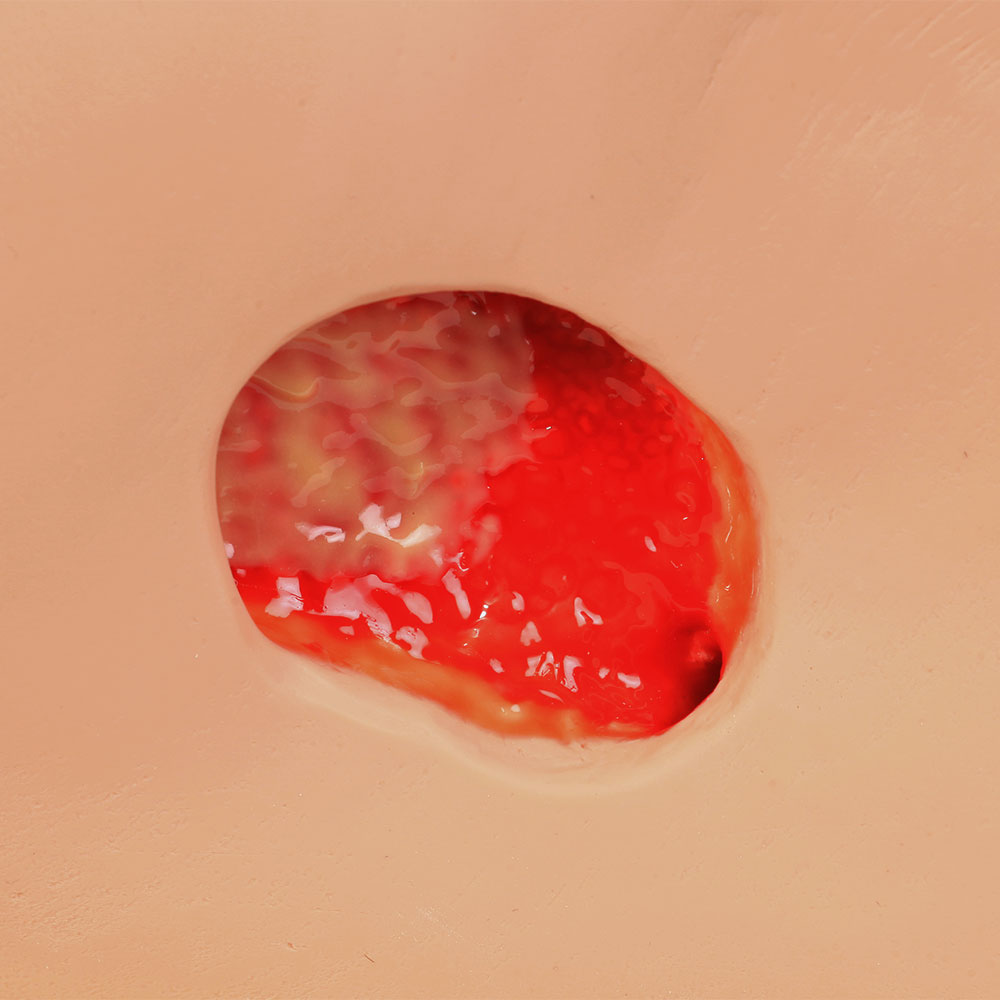

- Wound care simulation model displays the following pressure injuries:

- Stage 2

- Great care has been taken to hand paint each wound just as you would see it on a patient for the most life-like patient training scenario